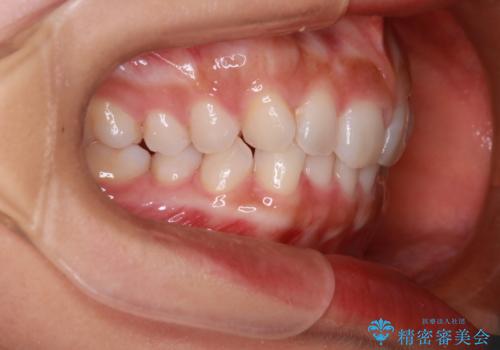

【インビザライン】前歯のねじれを治したい

- 前歯のガタガタを主訴に来院されました。

叢生の量は軽度でしたが臼歯の遠心移動を行い、インビザラインにて治療をしました。

叢生の改善に必要なスペースは遠心移動やIPRで作ることが可能です。今回は遠心移動をメインにスペースを作って叢生の改善を行いました。